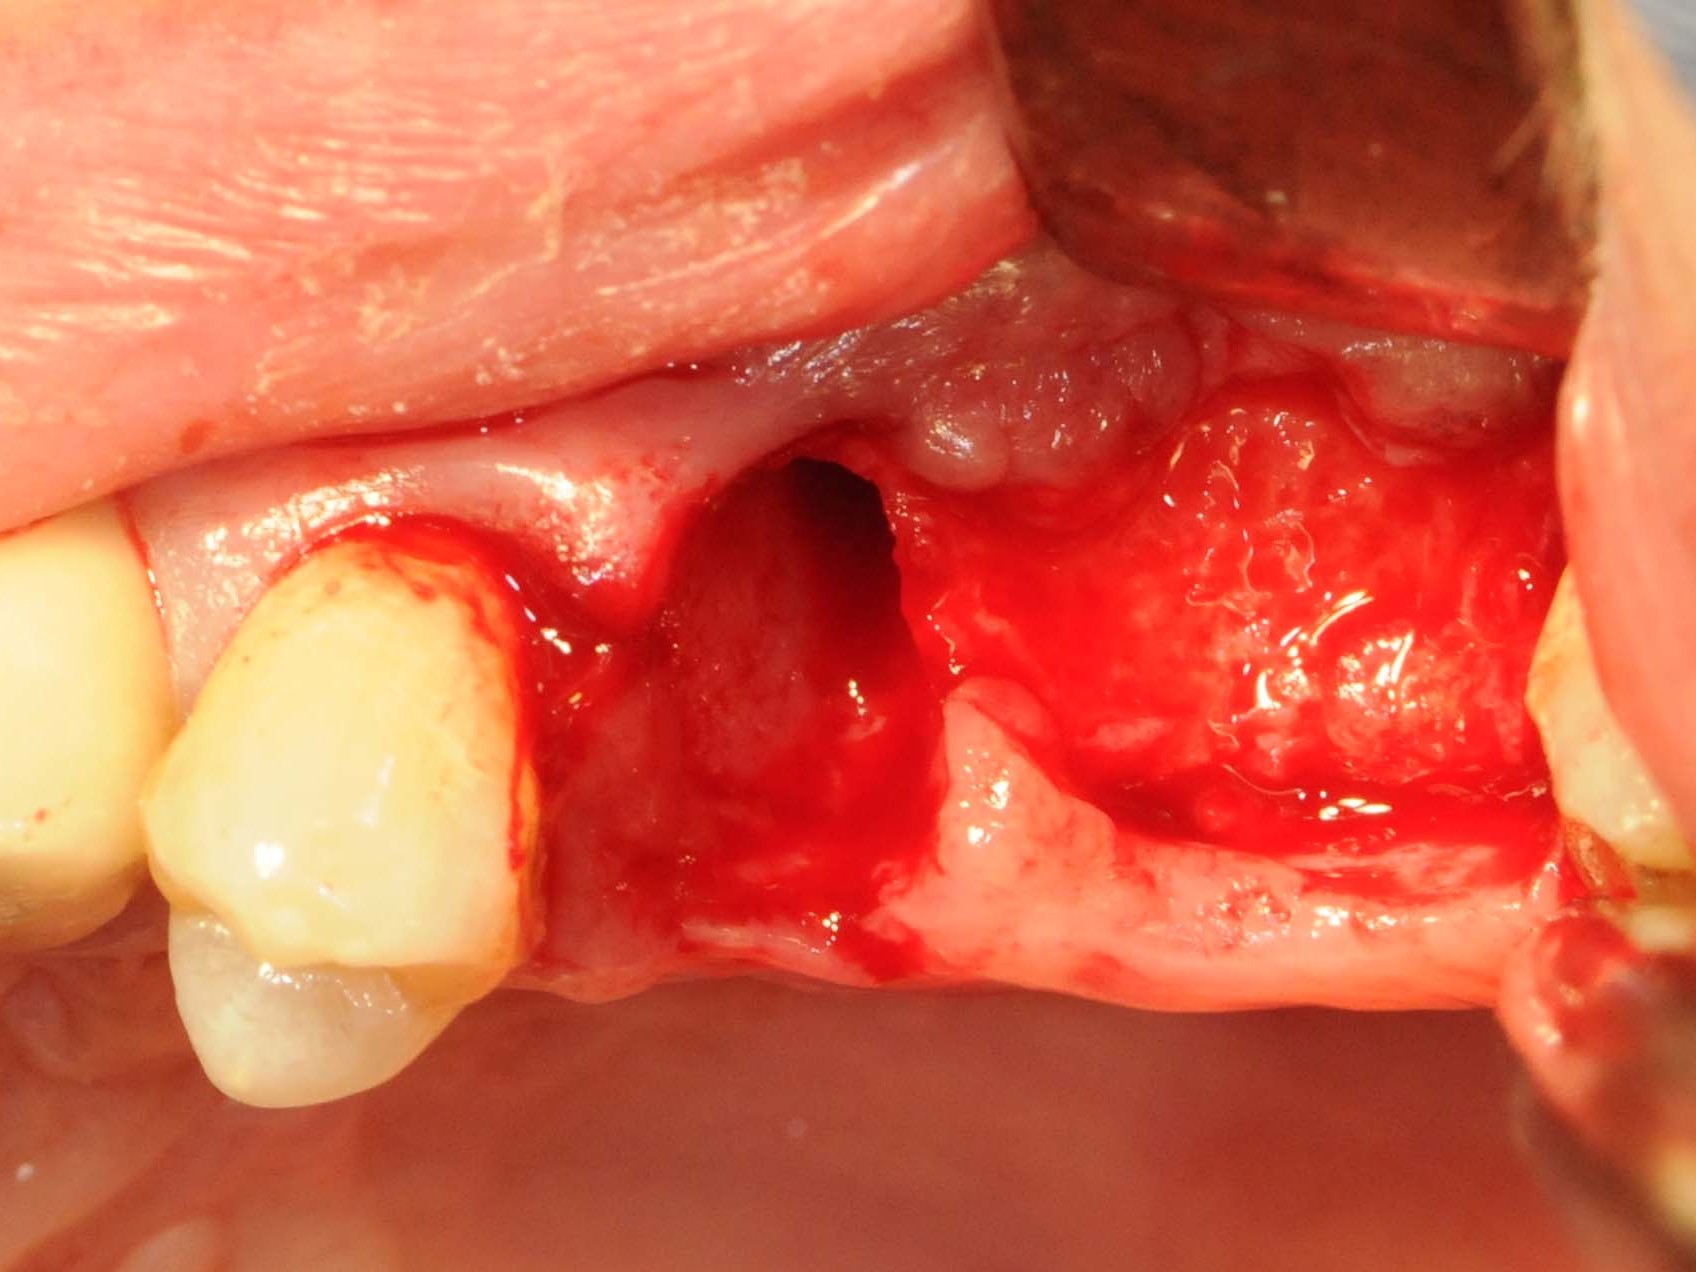

Unter oraler Antibiose mittels Clindamycin 600mg 2 x/Tag erfolgte zunächst die typische minimalinvasive Präparation des Mukoperiostlappens unter Erhalt der Papillen zu den Nachbarzähnen in Regio 12 (Abb. 6), nachdem die Brücke von Zahn 11 nach 14 entfernt wurde (Abb. 7). Wegen Nichtanlage von 13 steht der Zahn 14 in dessen Region. Seinerzeit wurde der Zahn 14 zur Aufnahme einer entsprechenden Eckzahnkrone umgestaltet. Die Implantatbettpräparation (Abb. 8 und 9) für das Straumann PURE Ceramic Implantat (Ø 3,3 mm, Länge 12mm) erfolgte gemäß dem Straumann Guided Surgery Protokoll. Die abschließende Implantatinsertion wurde dem Protokoll für die Straumann PURE Ceramic Implantatlinie gemäß durchgeführt (Abb. 10 und 11). In der Implantatsetzungsregion des zweiten Quadranten wurde zunächst die Inlay-Brücke von Zahn 25 nach 27 entfernt. Seitens des zahntechnischen Labors wurde das Zahninlay von Zahn 27 von der Brücke getrennt und wieder inkorporiert. Nach der Extraktion des tief zerstörten Zahnes 25 erfolgte die typische Mukoperiostlappenpräparation. Nach Darstellung des Insertionssitus kam die massive vestibuläre Knochendefizitsituation in Regio 26 zur Darstellung (Abb. 12). Zunächst wurde die Präparation der Implantatstollen in Regio 25 und 26 gemäß dem Straumann Guided Surgery-Protokoll durchgeführt. In Regio 25 wurde ein Straumann Bone Level Roxolid Implantat (Ø 4,1 mm, Länge 12mm) als Sofortimplantation eingesetzt (Abb. 13 und 14). In Regio 26 wurde ein Knochenring CHB¹⁶ zur Augmentation des vestibulären Knochendefizits entsprechend des ossären Knochenabhanges angeschrägt und in der Höhe eingekürzt (Abb. 15). Die Anpassung des homologen Ringes erfolgt unter Fixierung mit der bonering fix-Zange und Anwendung einer 10-mm-Diamanttrennscheibe (Abb. 16).

Abb 12 vestibuläre Knochendefizitsituation

Abb. 12: vestibuläre Knochendefizitsituation